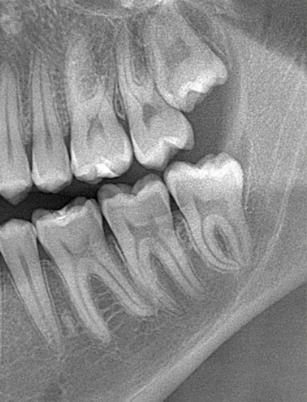

BIÓPSIAS,

TERCEIROS MOLARES

E IMPLANTODONTIA